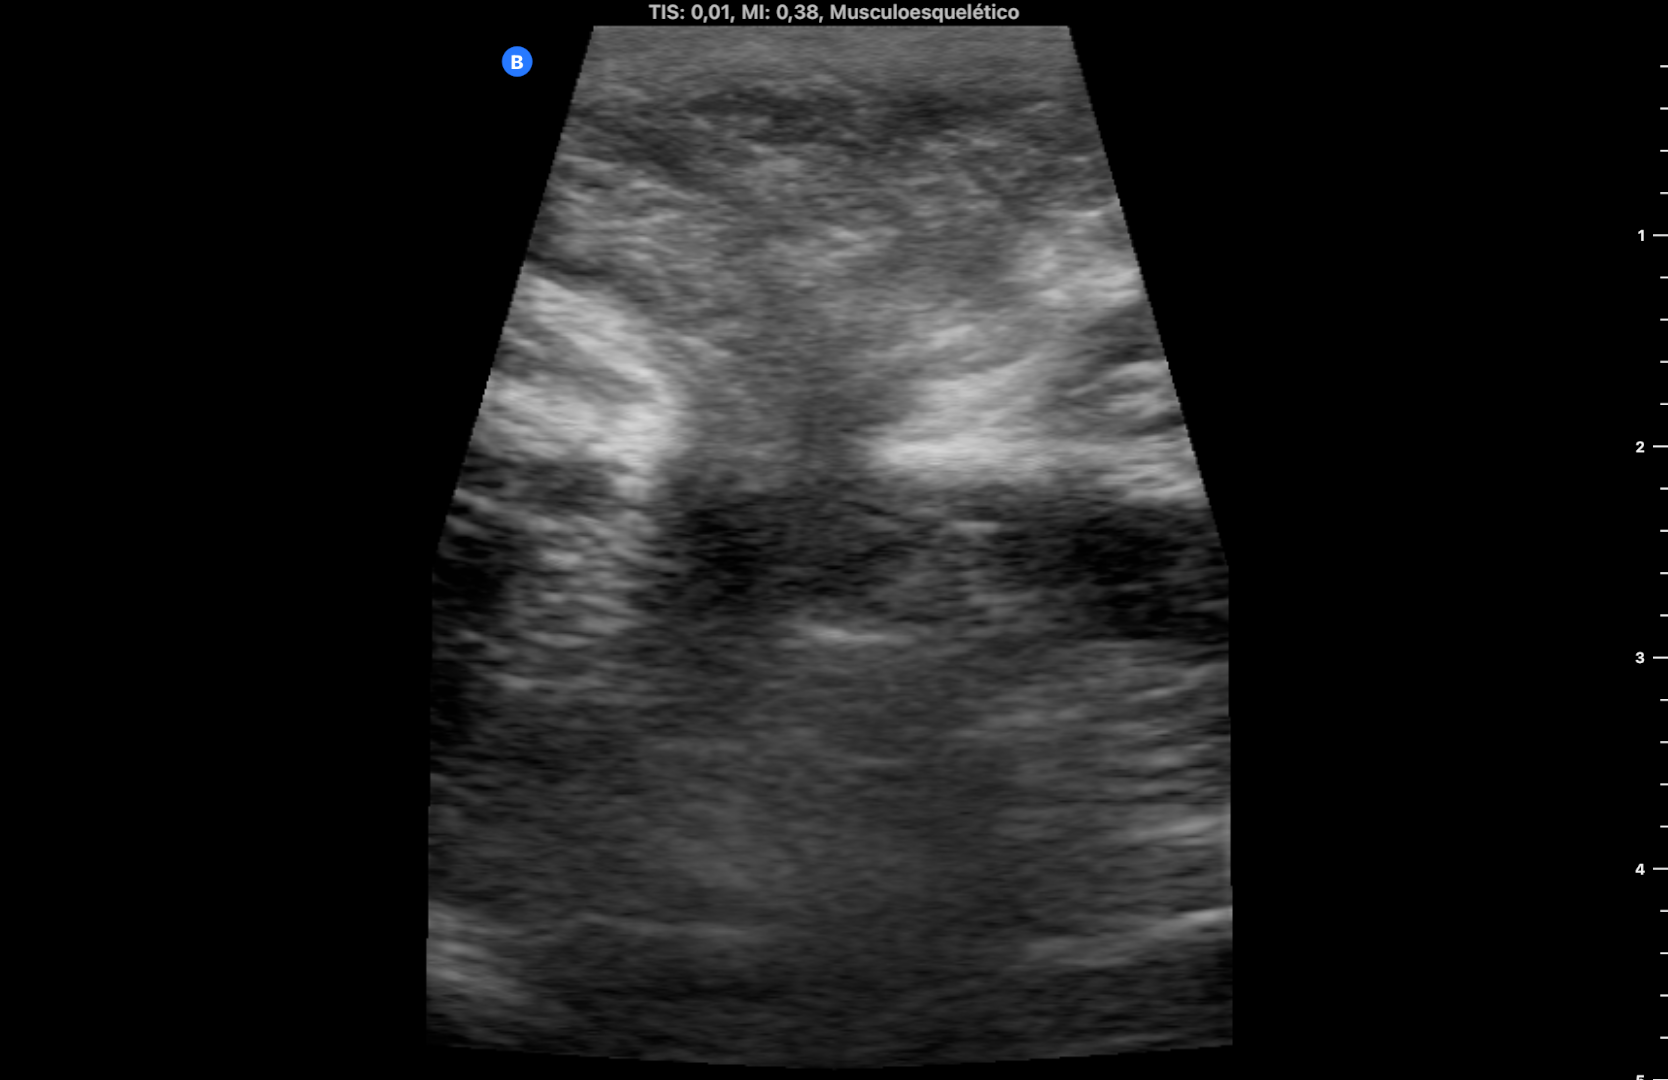

Se utiliza en la misma consulta una sonda portátil con preset de partes blandas, observando una imagen heterogénea redondeada, rodeada de líquido anecogénico a nivel subcutáneo que rompe la línea alba (imagen 1). Durante la exploración se comprime con la sonda en el lugar de la imagen consiguiendo la reducción de la misma y desapareciendo el dolor. La ecografía muestra entonces la discontinuidad de la línea alba con una pequeña protrusión de grasa (imagen 2) (se dispone de vídeos).